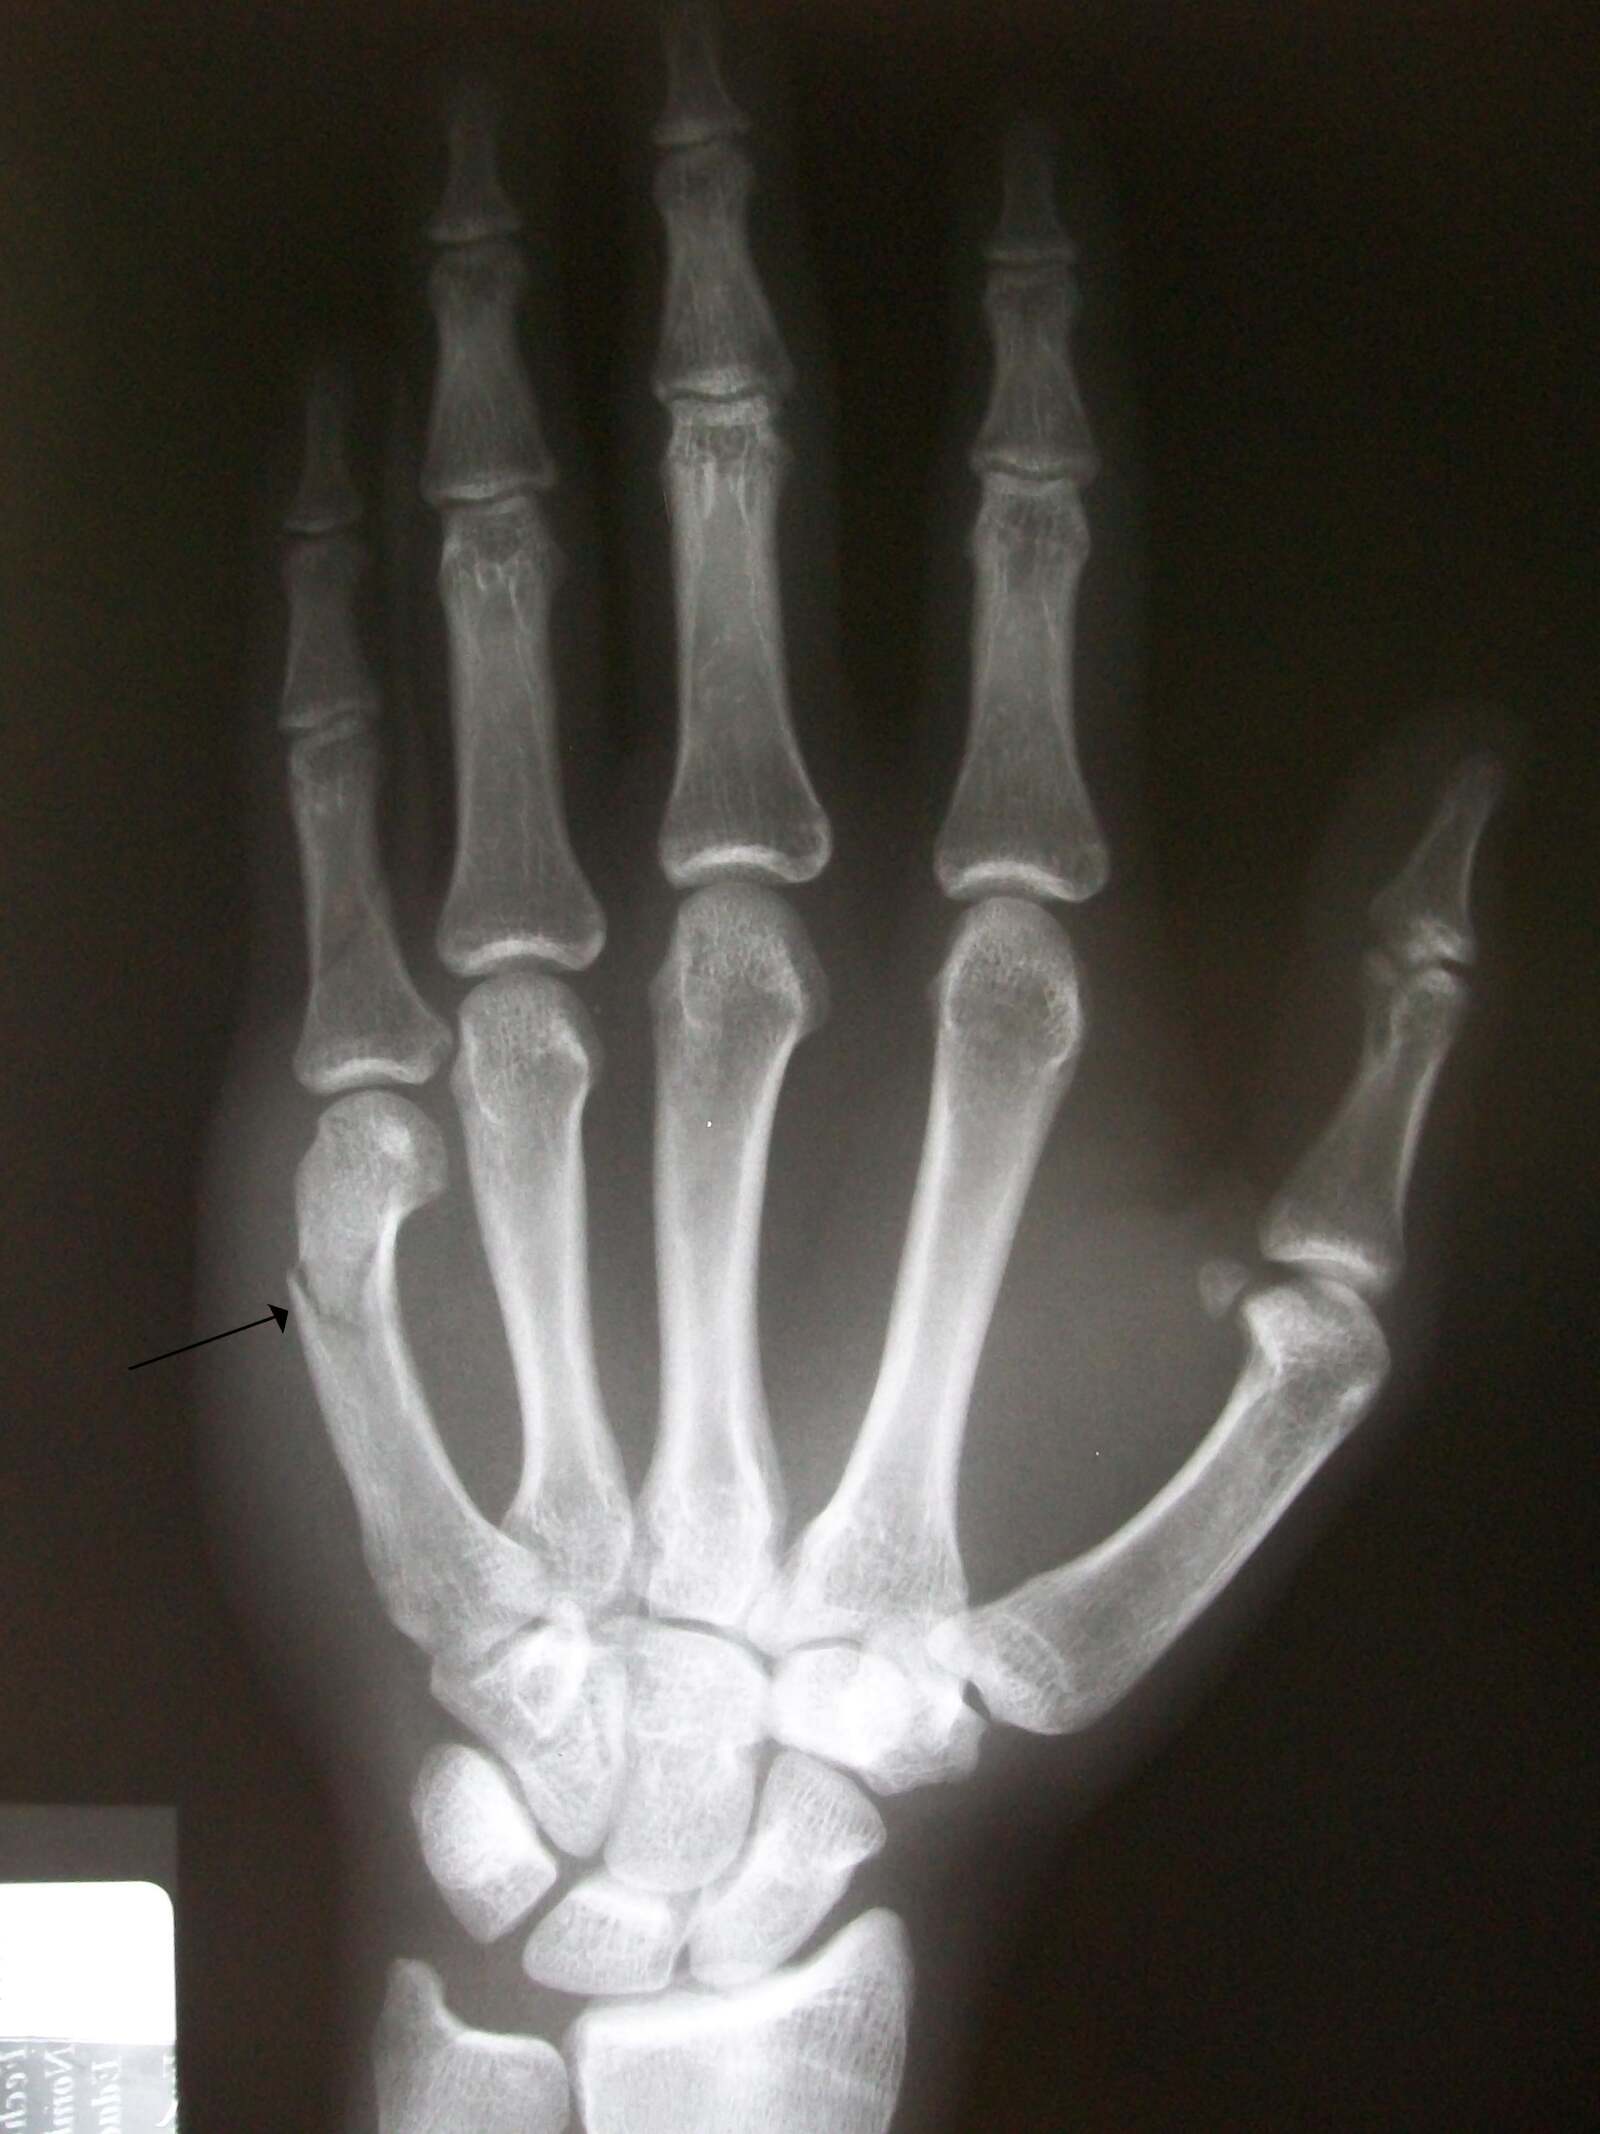

From radiopaedia.org

Boxer's fracture Image How Much Does A Boxer S Fracture Cost This bone connects the wrist to the base of the pinky finger. Causes include punching or smacking. a boxer's fracture, or metacarpal fracture, is a bone fracture that affects knuckles in the hand. boxer’s fracture is the fifth metacarpal neck fracture resulting from direct trauma to the clenched fist. a boxer’s fracture is a fifth metacarpal fracture. How Much Does A Boxer S Fracture Cost.